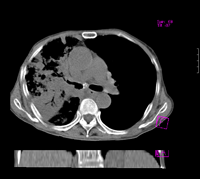

标题: CT9563:女67岁,咳嗽咯白痰伴纳差一月。右肺呼吸音低可闻及 [打印本页]

女67岁,咳嗽咯白痰伴纳差一月。右肺呼吸音低可闻及湿罗音。白细胞及淋巴细胞不高,无发烧

慢支,肺气肿,右肺结核,毁损肺.

考虑右肺细支气管肺泡癌可能,建议进一步检查

图片不全,考虑两肺tb,支气管肺泡癌不排除

病灶范围较大,病史较短,病人年龄较大,结核中毒症状不明显, 考虑1右肺细支气管肺泡癌,2.硬化性淋巴瘤,建议进一步检查